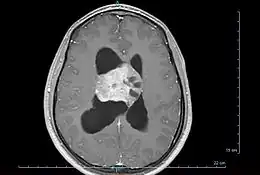

Cette tumeur est quasiment toujours exclusivement située dans le système ventriculaire cérébral (surtout aux niveaux des ventricules latéraux, moins souvent dans le 3e ventricule). Cette tumeur a la fâcheuse tendance à se développer au contact des foramens de Monro et ainsi à les obstruer, entraînant de ce fait une hydrocéphalie non communicante (obstructive), et engendrant cliniquement un syndrome d'hypertension intracrânienne.

Le diagnostic est réalisé grâce à l'imagerie cérébrale, scanner ou au mieux IRM cérébrale, retrouvant cette formation hétérogène à trois composantes en général (tissulaire +/- kystique et calcique), avec rehaussement partiel à l'injection de produit de contraste.

Elle permet d'étudier les rapports avec les zones fonctionnelles du cerveau (notamment le pilier du fornix, un des composants du circuit de Papez responsable de la mémoire antérograde), le système vasculaire (réseau veineux profond), ainsi que le retentissement de la tumeur sur le cerveau (effet de masse de par l'hydrocéphalie, œdème, hémorragie, engagement…).